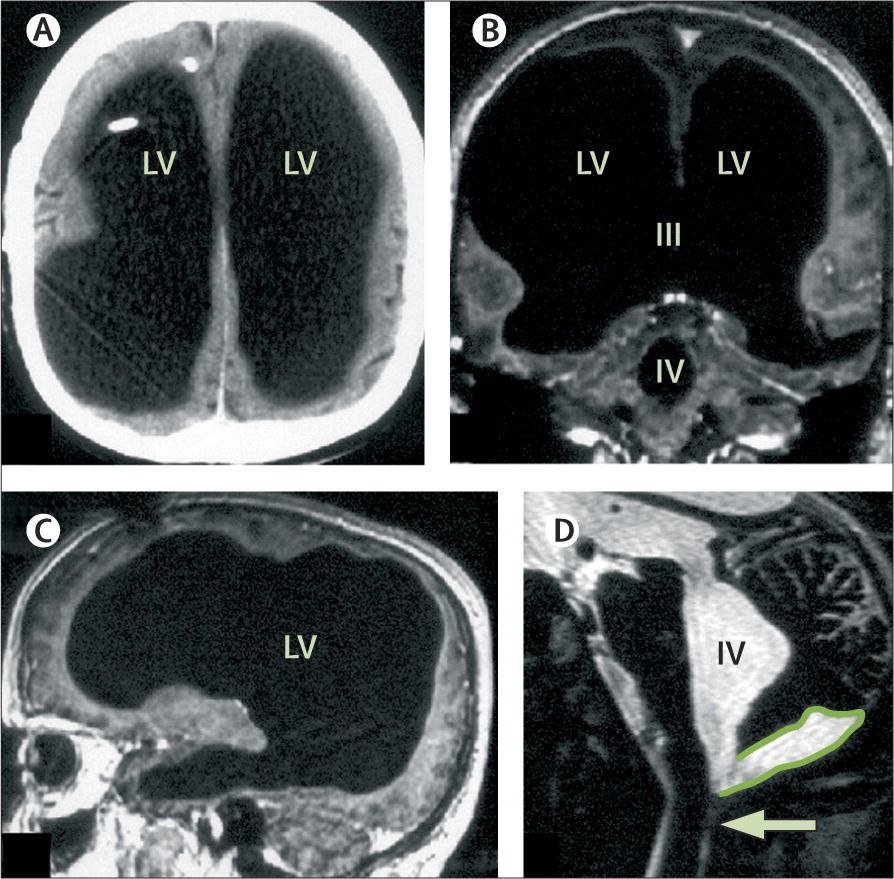

МРТ головного мозга пациента 44 лет.

44-летний француз обратился к врачу с жалобой на слабость в ноге. МРТ показала шокирующую картину: его череп был практически полностью заполнен жидкостью. Сохранился лишь тонкий слой мозгового вещества — около 10% от нормы (смотрите фотографию МРТ выше).

🟠В подростковом возрасте ему диагностировали гидроцефалию

🟠После удаления шунта жидкость постепенно "сжимала" мозг в течение 30 лет